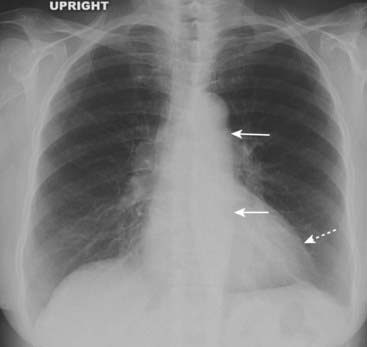

image

Figure 9-21 Chronic mitral stenosis with tricuspid regurgitation.

The left atrium is enlarged (solid white arrow). Pulmonary venous hypertension has produced a redistribution of flow in the lungs so that the upper lobe vessels have become more prominent than the lower lobe (cephalization) (white circle). Due to increased pulmonary vascular resistance and subsequent pulmonary arterial hypertension, the right heart also undergoes changes, eventually including tricuspid regurgitation with enlargement of the right atrium (solid black arrow).